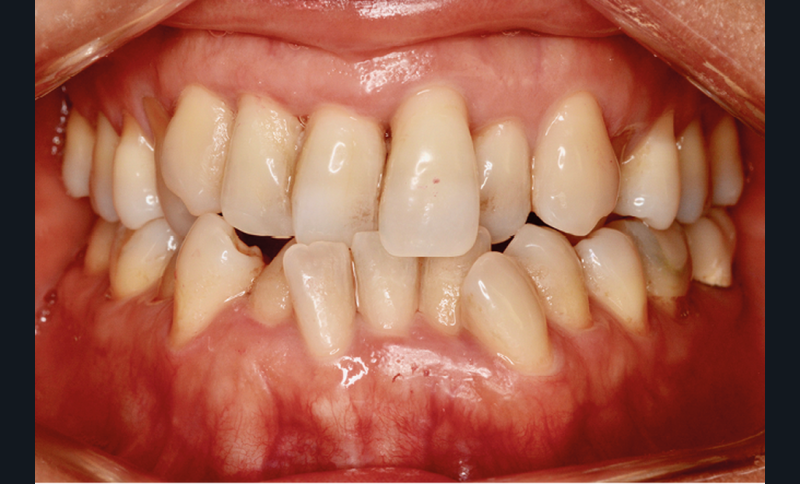

Présentation du cas (fig. 1 à 9)

Sur le plan squelettique, on retrouve une classe III de Ballard par hypomaxillie, dans un schéma facial hyperdivergent.

Sur le plan dentaire, la patiente est en classe III droite et gauche, canine et molaire de 6 mm, avec une occlusion inversée antérieure localisée à 11, 12 et 22. Elle présente une dysharmonie dents-arcades sévère, une agénésie d’une incisive mandibulaire est à signaler, et les troisièmes molaires ont été extraites à l’âge de 21 ans.

Au niveau fonctionnel, on note un bruxisme statique avec contact permanent entre les dents maxillaires et mandibulaires. La patiente présente des prématurités en relation centrée sur les incisives, le guidage en propulsion est perturbé et des interférences multiples sont retrouvées en latéralités droite et gauche.